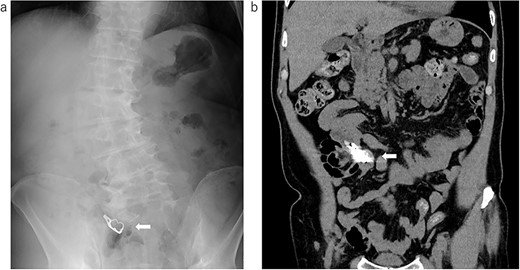

The image data were obtained by the previous doctor; (a) X-ray examination: the arrow shows the swallowed denture; (b) the coronal image of the CT: the arrow shows the swallowed denture.